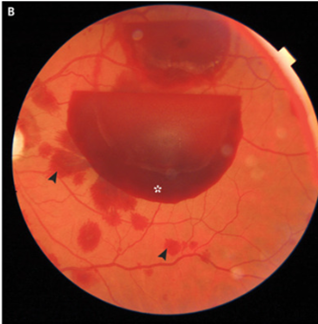

眼底検査施行され、両眼に網膜前出血を認めた。

右眼は網膜下出血(矢印)

両眼とも網膜内出血あり(矢印)